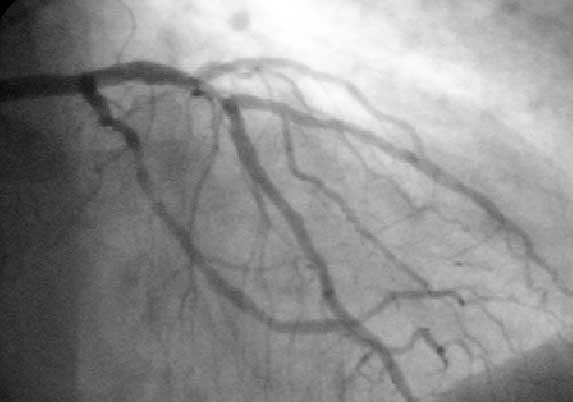

Percutaneous coronary intervention (PCI) is a non-surgical procedure used to treat narrowing of the coronary arteries of the heart found in coronary artery disease. The process involves combining coronary angioplasty with stenting, which is the insertion of a permanent wire-meshed tube that is either drug eluting (DES) or composed of bare metal (BMS). The stent delivery balloon from the angioplasty catheter is inflated with media to force contact between the struts of the stent and the vessel wall (stent apposition), thus widening the blood vessel diameter. After accessing the blood stream through the femoral or radial artery, the procedure uses coronary catheterization to visualise the blood vessels on X-ray imaging. After this, an interventional cardiologist can perform a coronary angioplasty, using a balloon catheter in which a deflated balloon is advanced into the obstructed artery and inflated to relieve the narrowing; certain devices such as stents can be deployed to keep the blood vessel open. Various other procedures can also be performed. Primary PCI is the urgent use of PCI in people with acute heart attack, especially where there is evidence of heart damage on the electrocardiogram. PCI is also used in people after other forms of myocardial infarction or unstable angina where there is a high risk of further events. Finally, PCI may be used in people with stable angina pectoris, particularly if the symptoms are difficult to control with medication. PCI is an alternative to coronary artery bypass grafting (CABG, often referred to as "bypass surgery"), which bypasses stenotic arteries by grafting vessels from elsewhere in the body. Under certain circumstances such as extensive blockages, background of diabetes, CABG may be superior. Coronary angioplasty was first introduced in 1977 by Andreas Gruentzig in Switzerland. PCI is used primarily to open a blocked coronary artery and restore arterial blood flow to heart tissue, without requiring open-heart surgery.